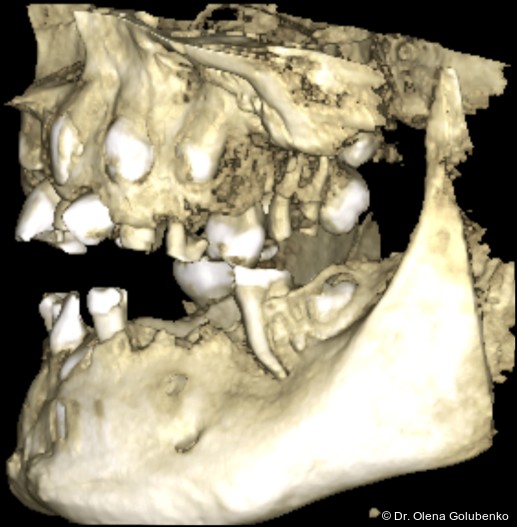

Der vorliegende Beitrag entstand aus einer kollegialen Anfrage: Eine 17-jährige Patientin mit ausgeprägten dentalen Auffälligkeiten wurde zur kieferorthopädischen Beratung überwiesen (Abb. 1a–c). Trotz zahlreicher vorangegangener zahnärztlicher Behandlungen war bis zu diesem Zeitpunkt keine syndromale Diagnose gestellt worden. Erst durch die sorgfältige Erhebung der allgemeinen und zahnmedizinischen Anamnese, die klinische Untersuchung sowie die gezielte Auswertung der dreidimensionalen Bildgebung ließ sich ein charakteristisches Muster erkennen. Auf dieser Grundlage ergab sich aus kieferorthopädischer Sicht der begründete Verdacht auf eine cleidokraniale Dysplasie, der die Vielzahl der dentalen, skelettalen und fazialen Befunde erstmals in einen schlüssigen klinischen Zusammenhang stellte.

Die dreidimensionale Bildgebung zeigt meist eine hohe Anzahl nicht durchgebrochener permanenter und überzähliger Zähne, die in unterschiedlicher Lage im Kiefer verbleiben (Abb. 3+4).

Die Diagnostik der cleidokranialen Dysplasie basiert auf einer sorgfältigen klinischen Untersuchung, der Analyse von Panoramaaufnahmen sowie insbesondere auf der digitalen Volumentomografie (DVT). Ziel ist es, die Anzahl, Lage, den Entwicklungsstand sowie mög­liche Interferenzen der retinierten und überzähligen Zähne präzise zu erfassen und in ei­nen funktionellen sowie skelettalen Kontext einzuordnen (Abb. 5–8).